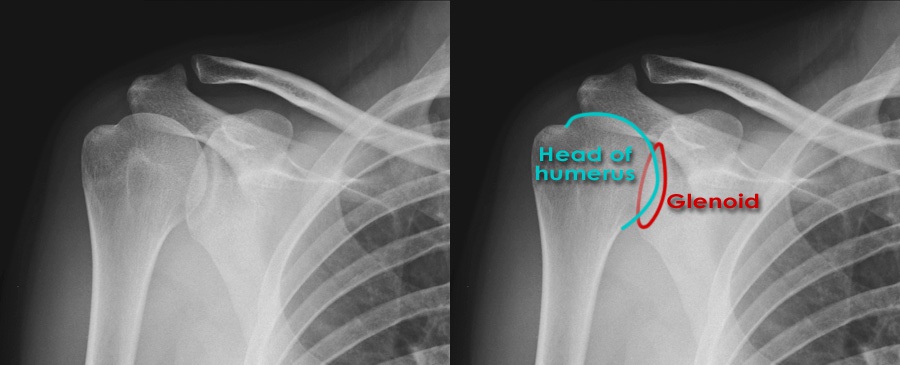

Рентген плеча: примеры снимков и их расшифровка